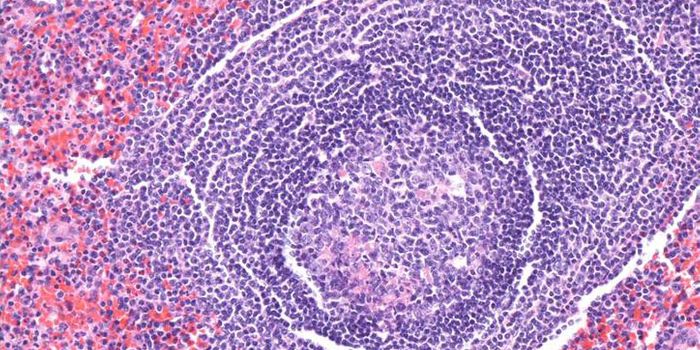

NOV 02, 2015ImmunologyB-cell leukemia occurs in 80-85 percent of children with acute lymphoblastic leukemia (ALL), a fast-growing cancer that ...